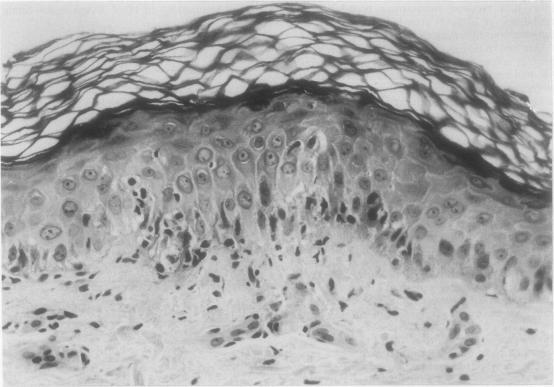

The histological appearances of skin and rectal biopsy specimens were studied in 31 bone marrow transplant recipients (13 autologous, 18 allogeneic) before transplant, at 28 days, at six months, and as soon as graft versus host disease (GVHD) was clinically suspected. Grades I and II skin changes were commonly seen in patients before transplant and in the autologous group after transplant, as well as in most of the allogeneic recipients with suspected GVHD. Epidermal lymphocytic infiltration was seen only in allogeneic recipients, with clinical GVHD following transplant, but this was not a consistent finding and no other histological features were seen which would distinguish early GVHD from changes caused by cytotoxic agents. Rectal biopsy specimens, however, were normal in patients before transplant and in autologous recipients at 28 days; single cell necrosis of crypt cells was seen only in six of 13 allogeneic recipients studied after transplant with clinical skin GVHD but no gastrointestinal symptoms. Skin changes greater than I and II are required for the histological diagnosis of GVHD. Rectal changes are more specific and may be present despite a lack of intestinal symptoms.

对31例骨髓移植受者(13例自体移植,18例异体移植)移植前、移植后28天、6个月以及临床怀疑发生移植物抗宿主病(GVHD)时的皮肤和直肠活检标本的组织学表现进行了研究。I级和II级皮肤改变常见于移植前的患者、自体移植组移植后的患者以及大多数疑似发生GVHD的异体移植受者。仅在移植后发生临床GVHD的异体移植受者中可见表皮淋巴细胞浸润,但这并非一致的发现,且未观察到其他可将早期GVHD与细胞毒性药物所致改变区分开来的组织学特征。然而,移植前的患者和28天时的自体移植受者的直肠活检标本均正常;在13例移植后出现临床皮肤GVHD但无胃肠道症状的异体移植受者中,仅6例可见隐窝细胞单细胞坏死。GVHD的组织学诊断需要皮肤改变大于I级和II级。直肠改变更具特异性,即使没有肠道症状也可能存在。